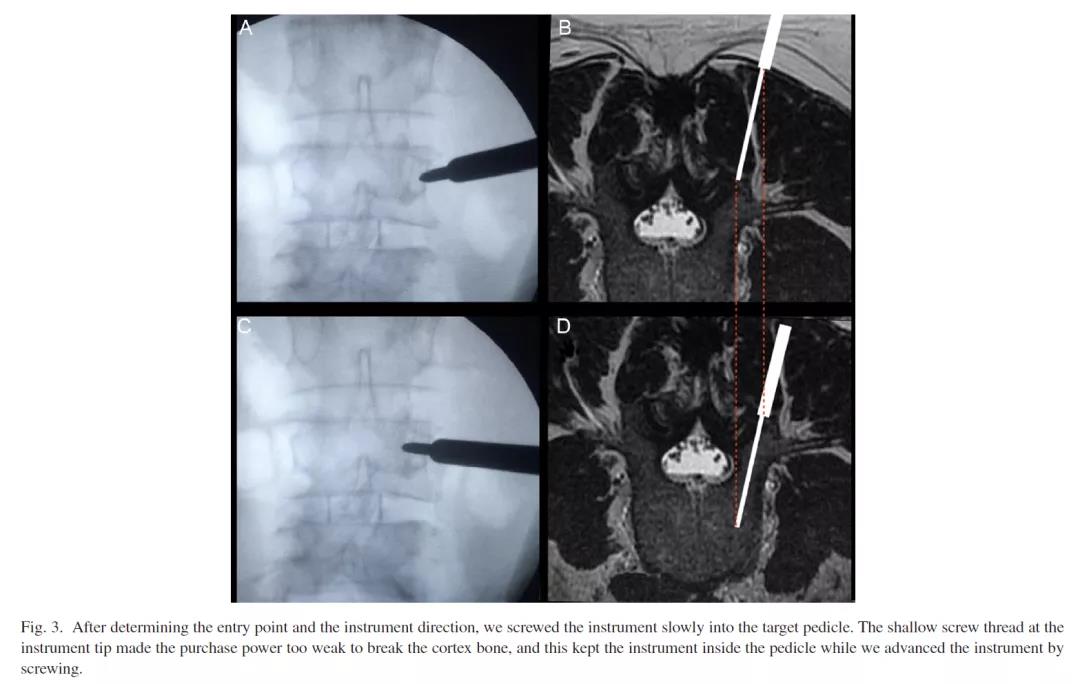

方法:①调整C臂位置,使需要穿刺的椎体呈现标准的正位影像,即终板影重叠成一直线,棘突位于正中。小技巧,此时C臂头尾倾的角度就是穿刺针的角度。②在穿刺针上进入套管3cm处做好标记。③正位透视找到进针点A点,将穿刺套管固定在此点上。④朝B点方向进入穿刺针,进入3cm后,正位透视穿刺针尖没有超过B点。⑤进阶:穿刺套筒探查上关节突与横突的交界点,向后向下2mm作为进钉点,根据CT大概测量椎弓根轴位(斜位)的角度,以此角度直接进入穿刺钉3cm,透视针尖不超过B点,可以透视一次完成一钉的植入(此法可能为目前世界上最快的经皮置钉方法)。